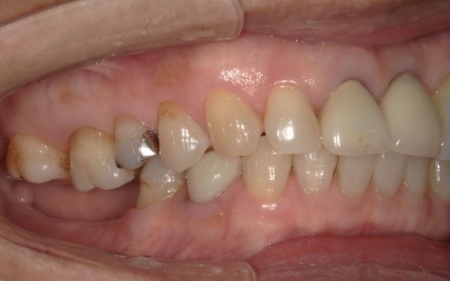

70代女性 歯根が折れた左上奥歯を抜いてインプラント治療で噛み合わせを回復した症例

まずは局所麻酔を行い、左上奥歯(第2小臼歯)を抜きます。

次に、抜歯した穴の状態を慎重に確認しながら、インプラント体を適切な深さと方向に埋入しました。今回は、抜歯と同時にインプラントを埋入する「抜歯即時埋入」を実施しています。

インプラントが顎の骨と結合したあと、人工歯を装着します。

また、手前の歯にも新しい被せ物を装着しました。

最後に、見た目や噛み合わせに問題がないことを確認し、治療を終了しています。